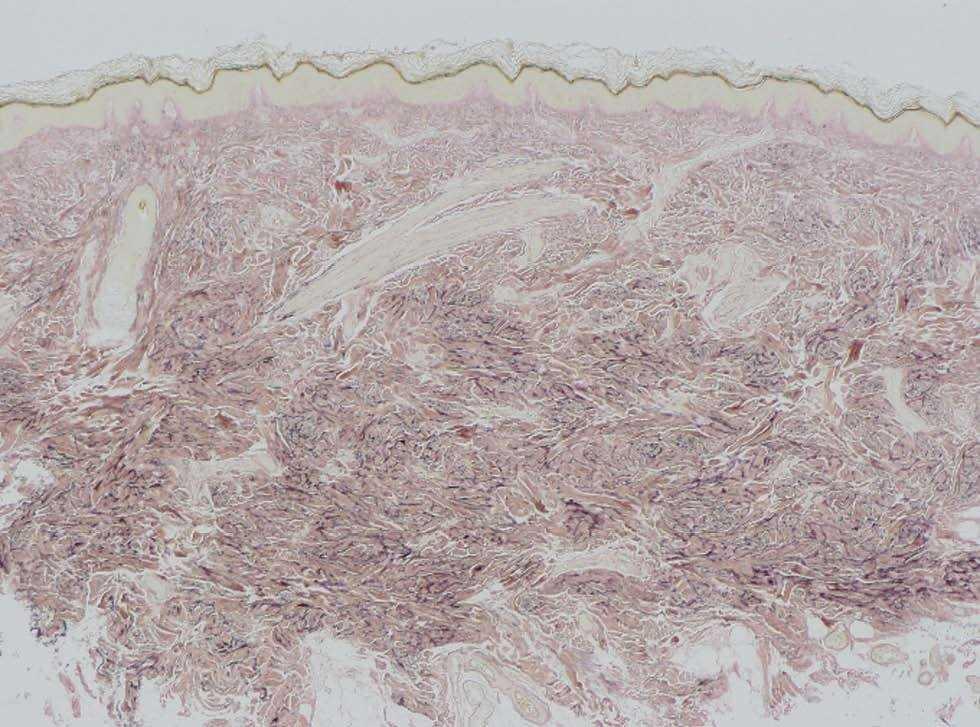

Una mujer de 41 años presentaba, como antecedentes de interés, un síndrome de la silla turca vacía, cataratas y osteopoiquilia. Como antecedente familiar de interés su madre estaba diagnosticada de esclerodermia. La paciente presentaba lesiones cutáneas asintomáticas desde el nacimiento, de distribución simétrica y bilateral, en muñecas y tobillos, que consistían en placas del color de la piel de consistencia firme y aspecto rugoso (fig. 1). La biopsia cutánea de una lesión mostraba un leve engrosamiento de la dermis. Con la técnica de Van Gieson se observó aumento de las fibras elásticas de la dermis reticular, con haces gruesos ramificados, compatible con un nevo elástico (fig. 2).

Fig. 2.--Aumento de fibras elásticas en la dermis reticular. (Van Gieson x4.)